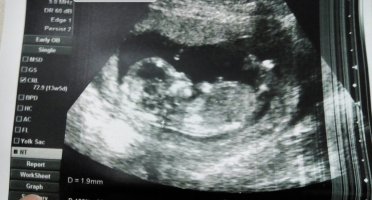

Bu bacak arası resmi 17.haftada sizce cinsiyet ne doktor erkeğe benzetti

• FBD144DA-B39E-4515-9DEA-102128A0A388.jpeg

FBD144DA-B39E-4515-9DEA-102128A0A388.jpeg

1.020,8 KB · Görüntüleme: 690